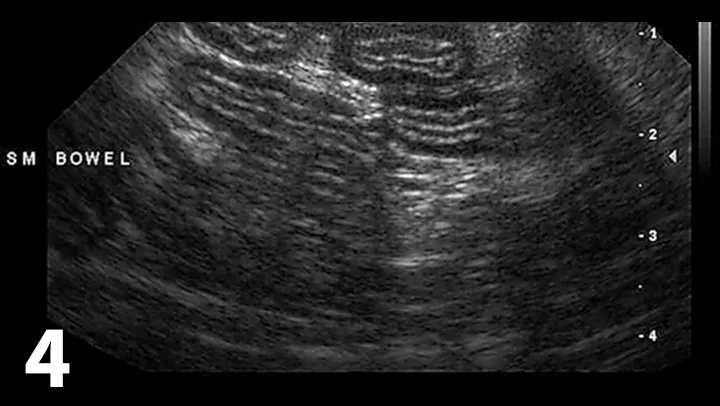

Assess for pancreatitis

• Abdominal ultrasound (Figure 3) may show ≥3 of the following features: evidence of pancreatomegaly, hypoechoic parenchyma, hyperechoic surrounding mesentery, irregular pancreatic border, dilation of pancreatic or bile ducts, dilation of the cystic duct, abdominal effusion

• A normal-appearing pancreas does not rule out pancreatitis

• Repeat abdominal ultrasound should be considered in light of pancreatitis being a dynamic disease process

An ultrasound image showing the pancreas of a veterinary patient, with measurements indicating a size of 1.40 cm. The pancreas is highlighted on the left side of the image, displaying its echogenic texture and surrounding anatomical structures.

Figure 3

Ultrasound highlighting several features of pancreatitis, including an enlarged pancreas with a hypoechoic parenchyma and hyperechoic surrounding mesentery, as well as a dilated pancreatic duct (arrow). These features are believed to represent acute pancreatitis.